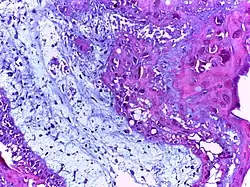

![]() |

Foreign body granuloma | Granulomatous reaction to keratin characterized by foreign body giant cells and chronic inflammatory cells. | Category: Histopathology of foreign body granuloma | Foreign body granuloma, silicone granuloma |